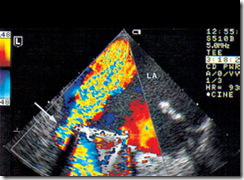

Ultrasound Pictures Mitral valve endocarditis, CDS demonstrates a paravalvular leak (arrow) causing regurgitation into the left atrium (LA)